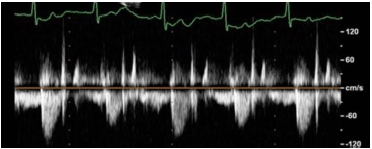

Em relação à figura a seguir, identifique a condição patológica evidenciada no fluxo aórtico na via de saída do VE.